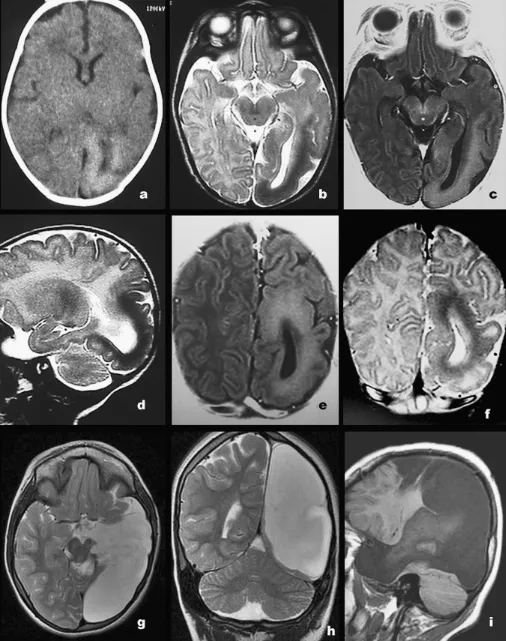

图1病例1(a、b)、病例2(c、d)与病例3(e、f)术前(a、c、e)及术后(b、d、f)轴位T2WI示患侧枕叶及颞顶叶容积缩小,伴弥漫性皮质不规则增厚:病例1、3以多小脑回为主,病例2为巨脑回;病变皮质与未髓化皮质下白质相比呈轻度低信号。术后图像可见颞-顶-枕区脑脊液充填的手术残腔。

图2病例4

a轴位CT:左侧颞、枕叶容积缩小,皮质显著增厚,以巨脑回为主;枕叶皮质光滑,脑沟回稀少,相对于未髓化皮质下白质呈轻度高密度(CT)、T1高信号(b、e)、T2低信号(c、d、f);左侧侧脑室异常扩大。

g–i术后MR(轴位T2、冠状T2、矢状T1):示颞-顶-枕区脑脊液充填手术残腔,病灶已完全切除。